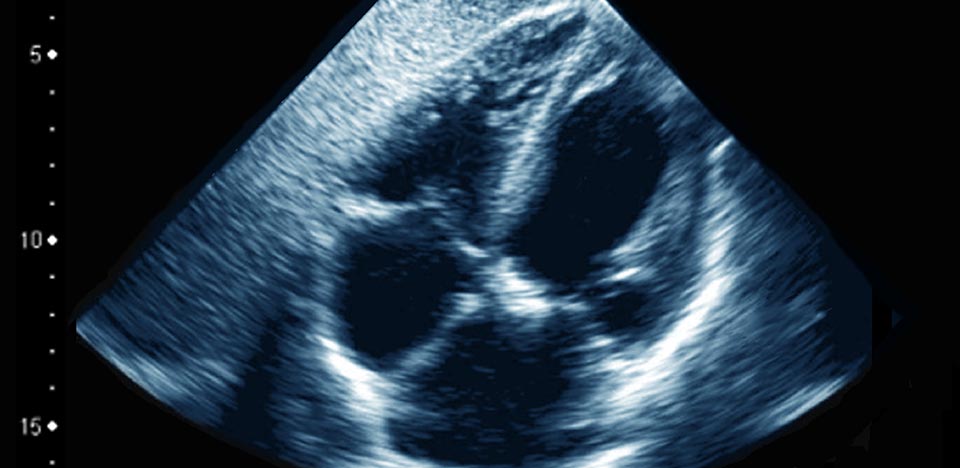

경기동물의료원 정밀심장센터는 반려동물의 선천성 및 후천성 심장질환을 전문적으로 진단하고 치료하는 심장 특화 센터입니다. 심장 초음파, 심전도, 방사선, Cardiac CT 등 정밀장비와 심장내과 전문 수의사의 풍부한 임상경험을 바탕으로 아이의 생명과 직결된 심장 질환을 정확하고 체계적으로 관리합니다.

심장 초음파 (Echocardiography)